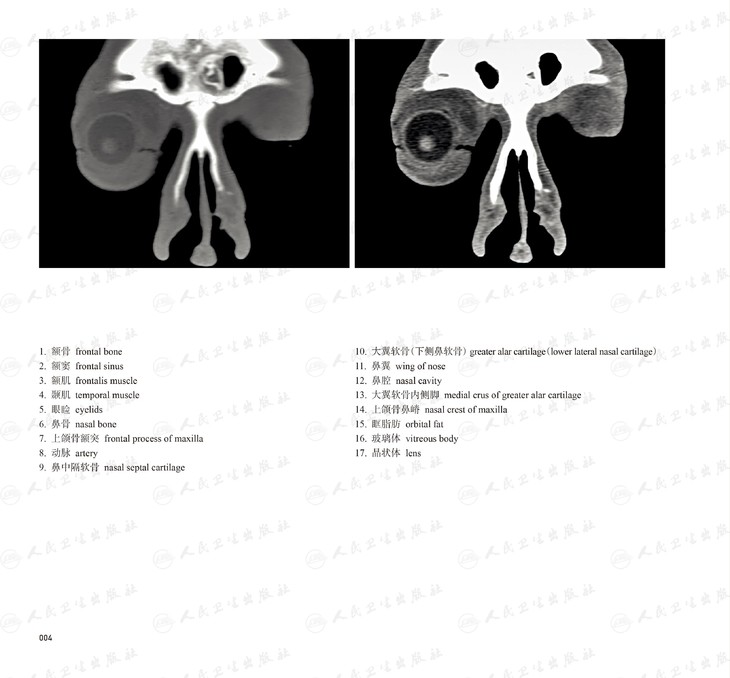

本书从数据集每隔1.2mm选取一幅图像,截取眼、耳、鼻及毗邻颅底的局部区域图像,共112幅图像。同时配以相应部位的CT图像对照。本书特色是断层解剖图利用数字图像处理技术优势,放大并清晰展示眼、耳、鼻及毗邻颅底断面的局部区域结构,组织色泽真实,甚至能够清晰显示肌肉纹理、筋膜纹路等细节结构,图像质量高于美国同类断层解剖彩色图的图像质量。对眼科、耳鼻咽喉科和神经内外科医生理解相关解剖结构有较大帮助。